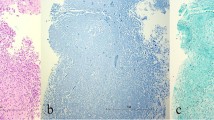

Idiopathic granulomatous mastitis (IGM) is a rare, benign inflammatory condition of the breast first reported by Kessler and Wolloch in 1972 [1]. It occurs primarily in women of childbearing age, most often in postpartum or breastfeeding mothers. The etiology of IGM remains elusive. Reports have suggested an association with autoimmune disease or the result of a directed response to trauma, metabolic or hormonal processes [2–5]. An association with Corynebacterium species has also been proposed [6, 7], though by definition, diagnosis necessitates exclusion of bacteria from microbiology and histology specimens. Histologically, IGM is characterized by non-necrotizing granuloma formation with a localized infiltrate of multi-nucleated giant cells, plasma cells, epithelioid histiocytes and lymphocytes [1, 2, 5, 8–10] (Fig. 1). A neutrophilic infiltrate may also occur with formation of organized microabscesses [2, 5].

A 27-year-old woman with an enlarging palpable right breast mass admitted to the hospital for intractable joint pain. An erythematous rash was noted on her right breast and extremities. She was 8 months post-partum, breastfeeding with difficulty on the right. Bilateral mediolateral oblique mammogram (a) demonstrates regional asymmetry in the middle depth upper breast (arrows). b Clinical photograph of the patient’s forearm shows erythematous areas (arrows), representing erythema nodosum. c Photomicrograph (original magnification ×200; haematoxylin-eosin [H-E] stain) showing non-necrotizing granulomatous inflammation (arrow) composed of histiocytes and giant cells

The mean age of IGM diagnosis was 44 years (range 25 to 72). Thirteen patients were premenopausal, all with prior full term pregnancies. Four patients were postmenopausal. The most common clinical presentation was a new enlarging unilateral breast mass (n = 14) (Fig. 1). Two patients had either skin ulceration with draining sinus tracts (Fig. 2) or a raised skin lesion with associated palpable masses (Fig. 3). Less common complaints included pain, erythema, nipple discharge, nipple retraction and axillary fullness. Two patients had skin lesions seen on the upper extremities consistent with erythema nodosum (Fig. 1). Four patients were asymptomatic with an abnormality detected on screening mammography. All cases but one were unilateral; bilaterality was unexpectedly identified at MRI with ill-defined masses demonstrated in both breasts of a 36-year-old premenopausal patient (Fig. 4).

IGM is a diagnosis of exclusion requiring careful histopathology review of biopsy specimens, as well as microbiological analysis. This rare inflammatory process is characterized by non-necrotizing granuloma formation in breast lobules (Fig. 1c). Necrosis is rare, a finding more typically seen with tuberculous mastitis [2, 10, 23, 24]. An associated inflammatory infiltrate composed of multi-nucleated giant cells, plasma cells, epithelioid histiocytes, and lymphocytes are typically isolated within affected lobules [4, 5, 10, 23] (Fig. 1c). Depending upon severity, this inflammatory response may extend into adjacent breast lobules. Involved parenchyma demonstrates loss of acinar structure and damaged ducts [2, 24]. A neutrophilic infiltrate and formation of sterile microabscesses may also be demonstrated [2, 19, 23].